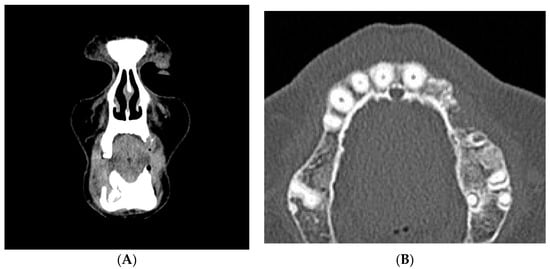

- Bedogni, A.; Fedele, S.; Bedogni, G.; Scoletta, M.; Favia, G.; Colella, G.; Agrillo, A.; Bettini, G.; Di Fede, O.; Oteri, G.; et al. Staging of osteonecrosis of the jaw requires computed tomography for accurate definition of the extent of bony disease. Br. J. Oral Maxillofac. Surg. 2014, 52, 603–608. [Google Scholar] [CrossRef] [PubMed]

- Wilde, F.; Heufelder, M.; Lorenz, K.; Liese, S.; Liese, J.; Helmrich, J.; Schramm, A.; Hemprich, A.; Hirsch, E.; Winter, K. Prevalence of cone beam computed tomography imaging findings according to the clinical stage of bisphosphonate-related osteonecrosis of the jaw. Oral Surg. Oral Med. Oral Pathol. Oral Radiol. 2012, 114, 804–811. [Google Scholar] [CrossRef] [PubMed]